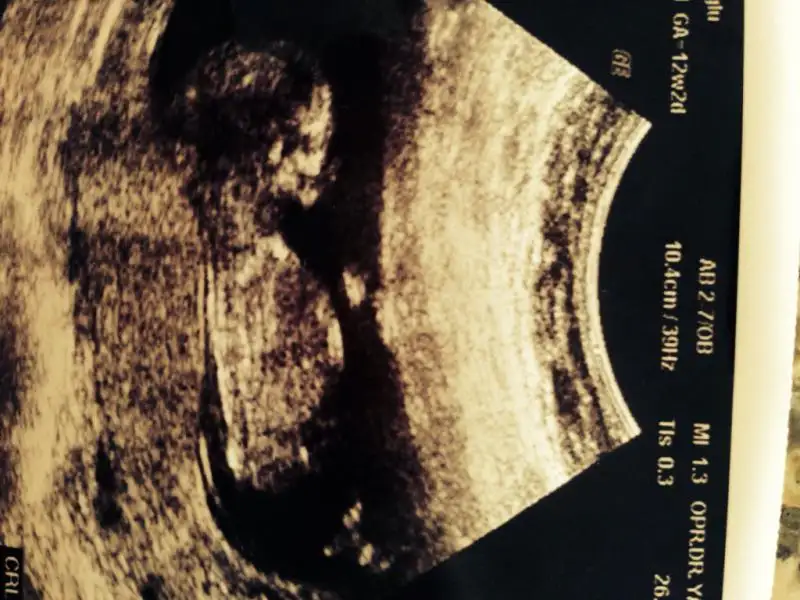

Kızlar 10+1 günlük bu görüntü şuan 12 +1 olduk pazartesi kontrol var ama sabırsızlanıyorum sizce nedir

Kadınlar Kulübü Mobil uygulaması kullanılarak gönderilmiştir.

tam paralel benim gördüğüm erkek gibi cnm.

simdi nedir bu genital nub

Eki Görüntüle 473828 gordugunuz gibi ust taraftaki simgedende anlasildigi gibi eger cikinti paralel ise kiz

yok 30°lik bir aciyla yukari dogru bakiyorsa %99 oglunuz olacak demektir